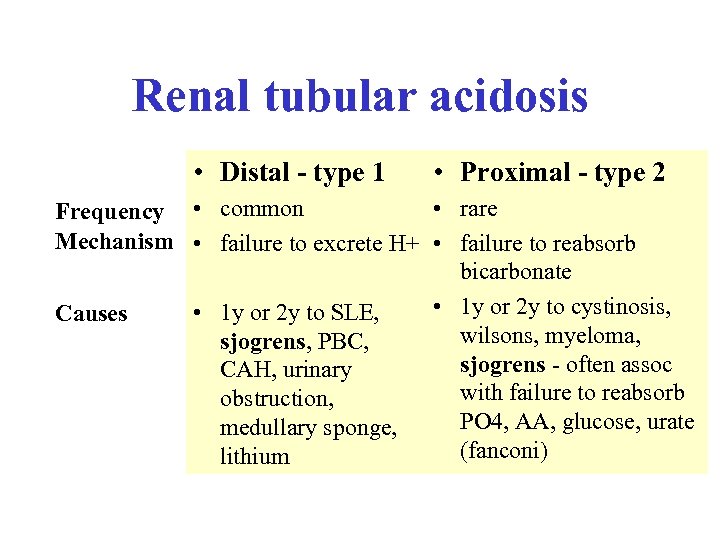

Renal tubular acidosis • Distal - type 1 • Proximal - type 2 • rare Frequency • common Mechanism • failure to excrete H+ • failure to reabsorb bicarbonate • 1 y or 2 y to cystinosis, • 1 y or 2 y to SLE, Causes wilsons, myeloma, sjogrens, PBC, sjogrens - often assoc CAH, urinary with failure to reabsorb obstruction, PO 4, AA, glucose, urate medullary sponge, (fanconi) lithium

Renal tubular acidosis • Distal - type 1 • Proximal - type 2 • rare Frequency • common Mechanism • failure to excrete H+ • failure to reabsorb bicarbonate • 1 y or 2 y to cystinosis, • 1 y or 2 y to SLE, Causes wilsons, myeloma, sjogrens, PBC, sjogrens - often assoc CAH, urinary with failure to reabsorb obstruction, PO 4, AA, glucose, urate medullary sponge, (fanconi) lithium